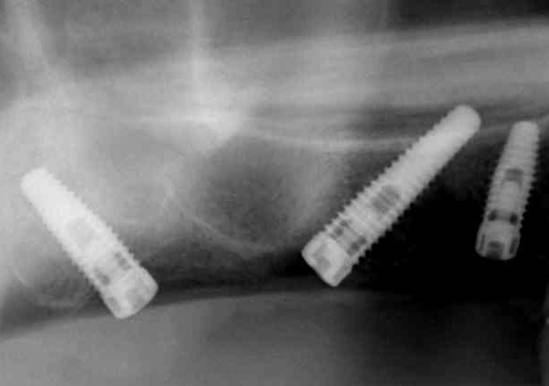

↓上顎洞の前壁を避けるように傾斜埋入されたインプラント。

↓上顎洞を避けるように傾斜埋入されたインプラント。